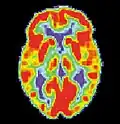

Maladie d'Alzheimer

La maladie d'Alzheimer (MA) est une maladie cérébrale progressive, dégénérative et fatale, dans laquelle est recensée une perte importante des cellules. Par conséquent, la mort des cellules cérébrales survient, bien que cette maladie soit la forme de démence la plus répandue[10]. À travers le monde, il existe 1 à 5 % de la population atteinte de la maladie d'Alzheimer[11]. Il est estimé que 500 000 Canadiens souffrent actuellement de la maladie d'Alzheimer ou d'une autre démence liée. Elle est la cause de handicap la plus répandue chez les individus âgés de 65 ans ou plus[10]. Les femmes sont disproportionnellement atteintes par cette maladie[12].